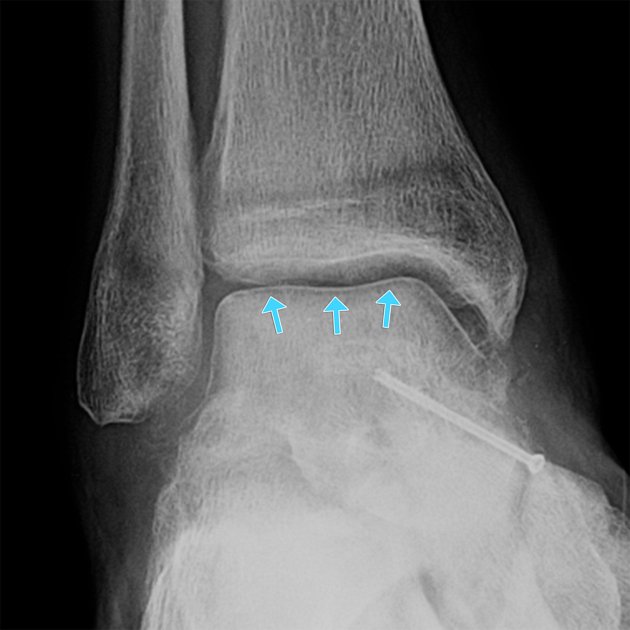

Here are intraop & postop images of yesterday's case by Dr. Jan Szatkowski @orthotraumamd and @IU_Health. INTRA-ARTICULAR DISTAL TIBIA FRACTURE IN 40F PROCEDURE: ORIF OF INTRA-ARTICULAR DISTAL TIBIA FRACTURE, ORIF FIBULA Here is the link to the clinical presentation and the…